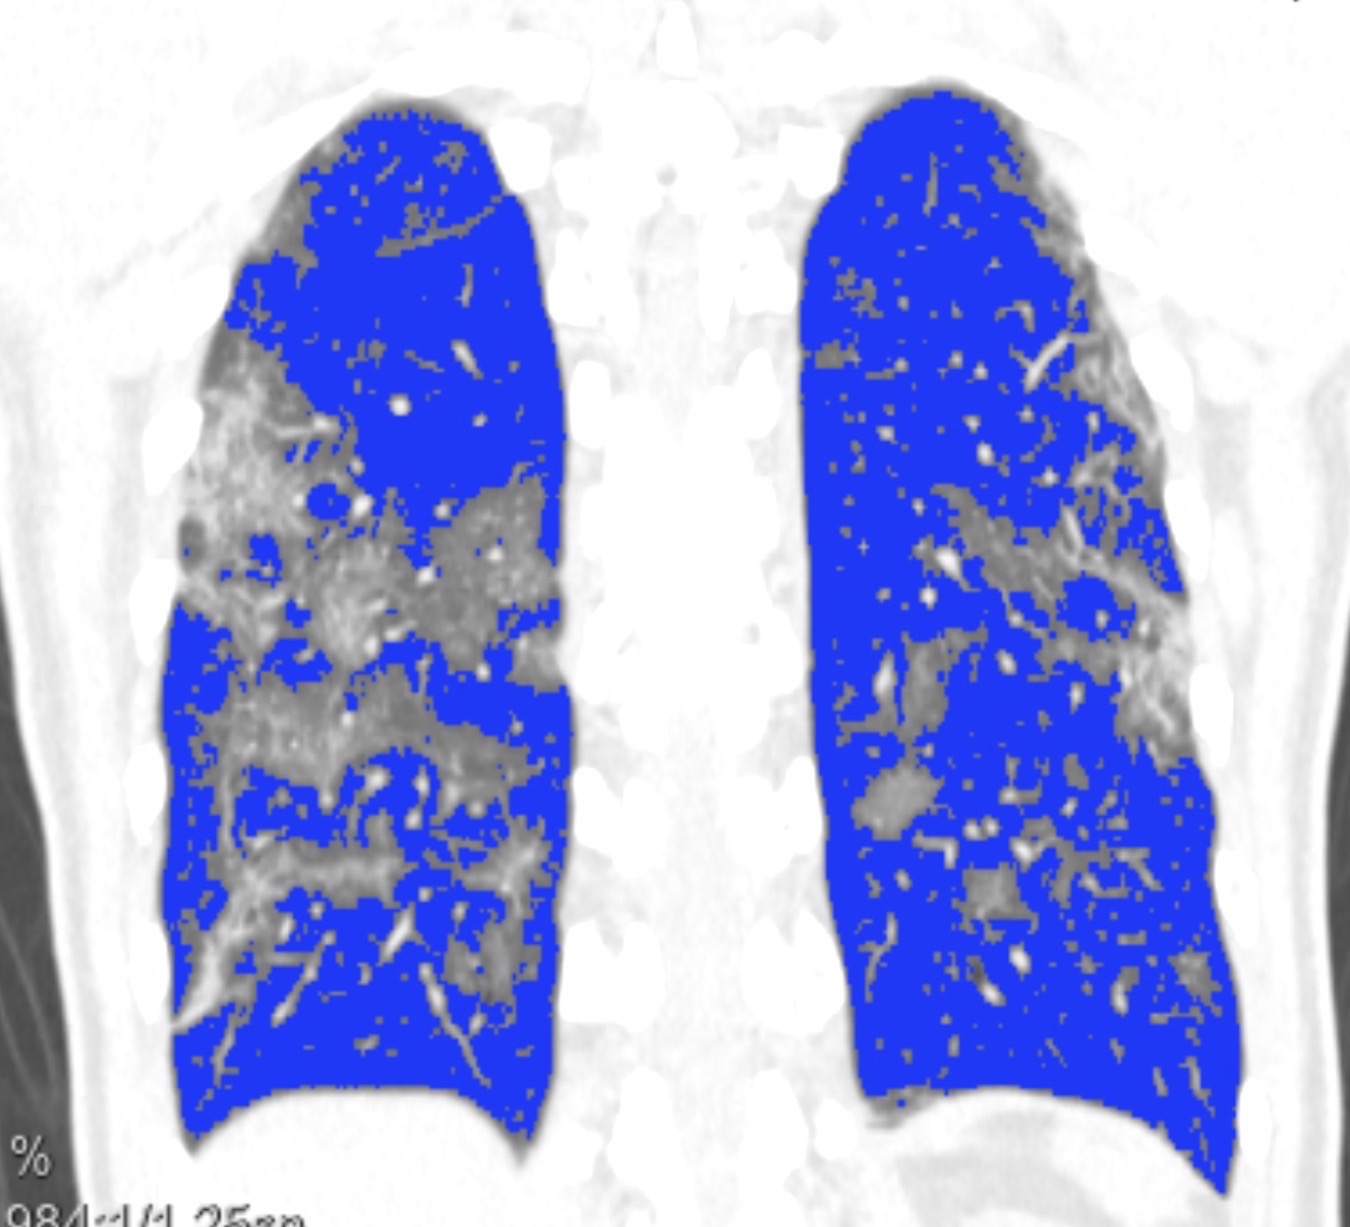

Grâce à la quantification semi-automatique cette atteinte peut être évaluée. Elle est estimée à environ 20% du volume pulmonaire total.

Quantification semi-automatique du degré d’atteinte :

Poumon sain en bleu, poumon malade non coloré

Sur le volume pulmonaire total, l’atteinte est quantifiée à 19,9%.

La quantification de l’atteinte est importante et révélatrice du niveau de gravité même si la clinique prime. Elle peut être minime (<10%), modérée (10-25%), étendue (25-50%), importante (50-75%) ou critique (>75%).